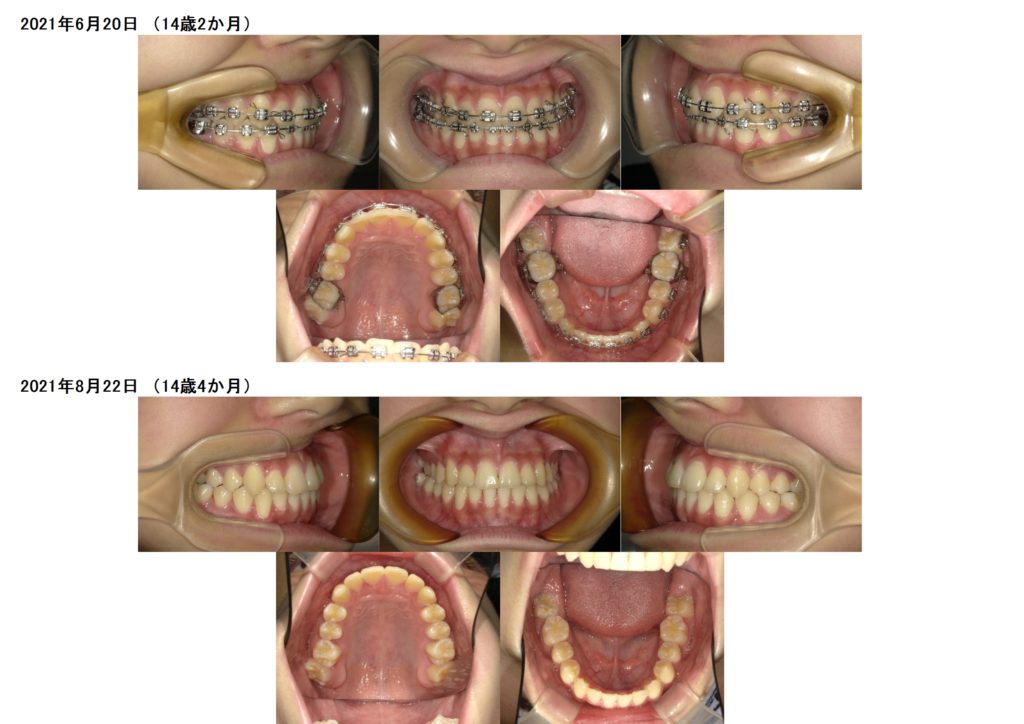

こんな感じでキレイな歯並び、噛み合わせになりました。

お子様の矯正治療の場合、

取り外し式の装置や、歯の裏側に入る装置などを使用し成長をコントロールしながら永久歯の生えるスペースの確保や噛み合わせの改善を行っていきます。